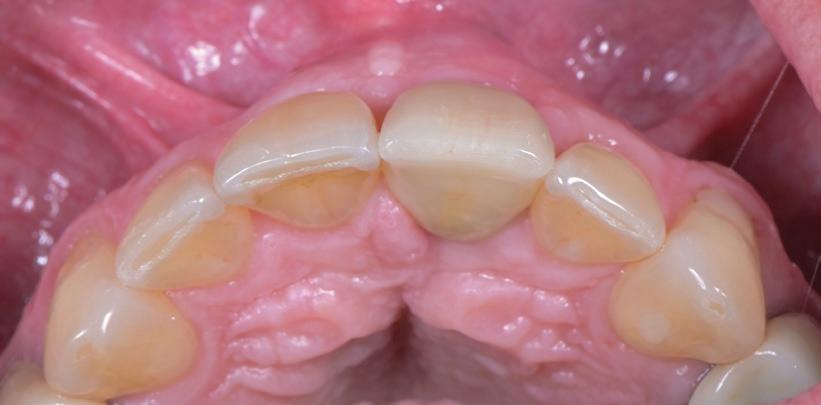

SITE AUGMENTATION Reconstituirea țesutului moale periimplantar și papilar în zona estetică

RECONSTITUIREA țesuturilor moi periimplantare. Scopul acestui raport de caz este de a demonstra procedurile chirurgicale utilizate pentru corectarea unui defect al țesuturilor moi periimplantare folosind țesutul moale interdentar în combinație cu tuberozitatea ca locație donatoare de țesut conjunctiv, utilizând o abordare prin tunelizare într-o zonă estetică.

Totuși, ca și în cazul implanturilor de titan, în rare cazuri, și la cele ceramice poate apărea o recesie nedorită cu expunerea umărului implantar. Cu toate acestea, din punct de vedere estetic, această recesie a gingiei inflamate este posibil să fie mult mai bine tolerată de către pacienții preocupați de marginile întunecate ale implanturilor de titan (fig. 2).

Trebuie remarcat, totuși, că în cazul implanturilor ceramice, ca și în al celor de titan, cementita, adică inflamația periimplantară cauzată de reziduurile de ciment, poate duce la periimplantită. În plus, la implanturile din dioxid de zirconiu poate apărea supraîncălzirea la înșurubarea implantului în os, iar suprafețele excesiv de aspre sau poroase ale implantului pot cauza defecte osoase periimplantare din cauza termoconductivității reduse a materialului. Deși sunt necesare mai multe dovezi științifice care să demonstreze o tendință mai scăzută spre periimplantită în cazul implanturilor ceramice, argumentul esențial pentru aceste implanturi bazat pe experiența clinică este starea excelentă și aproape constant lipsită de inflamație a țesuturilor moi periimplantare (fig. 3).